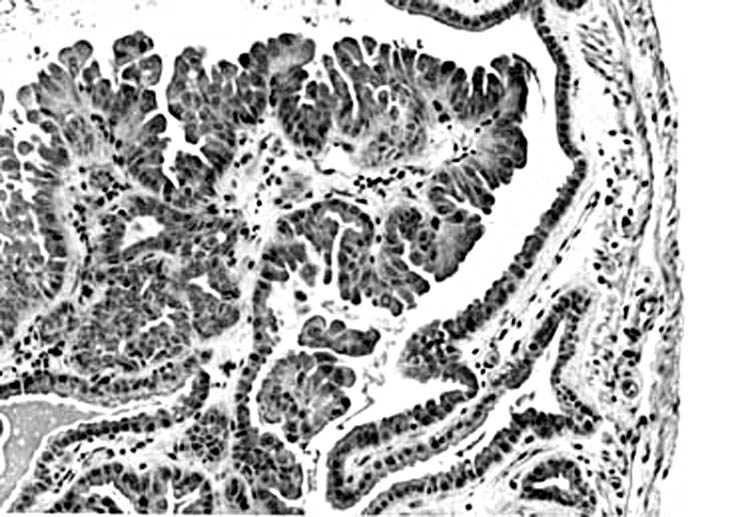

A papillary adenoma of the gallbladder in an adult mouse. Higher magnification reveals multiple layers of proliferating epithelium lining a connective tissue stalk.